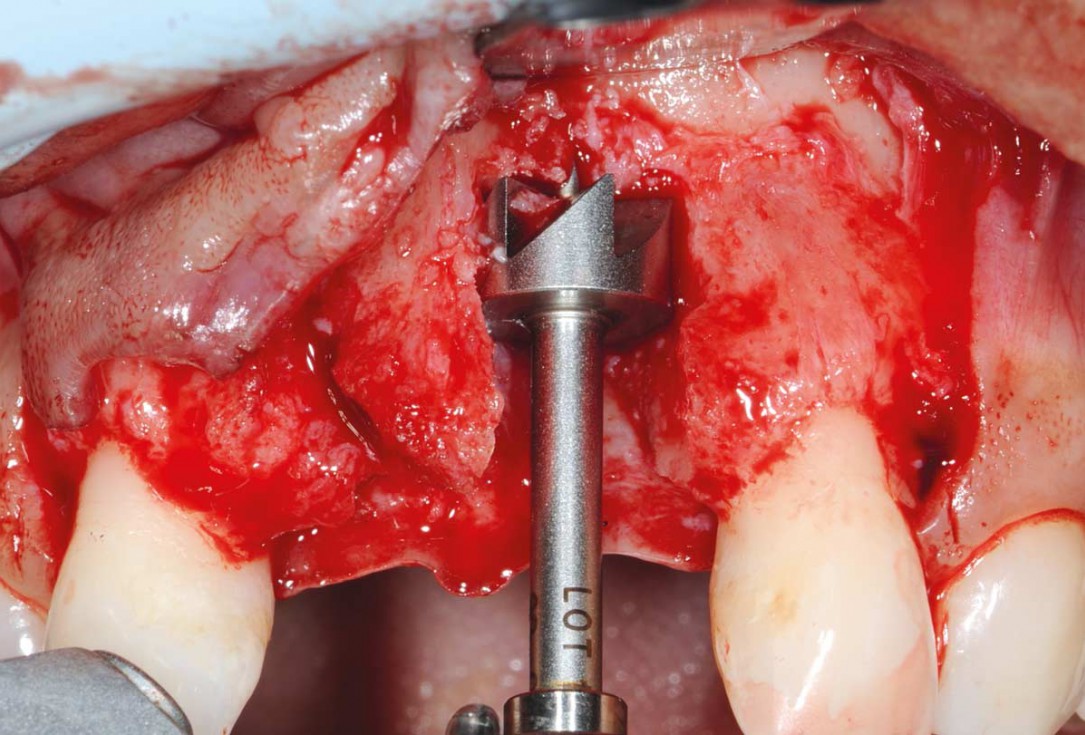

3/26 - Big bone defect visible after opening the flapBone augmentation in aesthetic zone with maxgraft® bonering - Dr. A. Patel

4/26 - Determine the defect size with the trephineBone augmentation in aesthetic zone with maxgraft® bonering - Dr. A. Patel